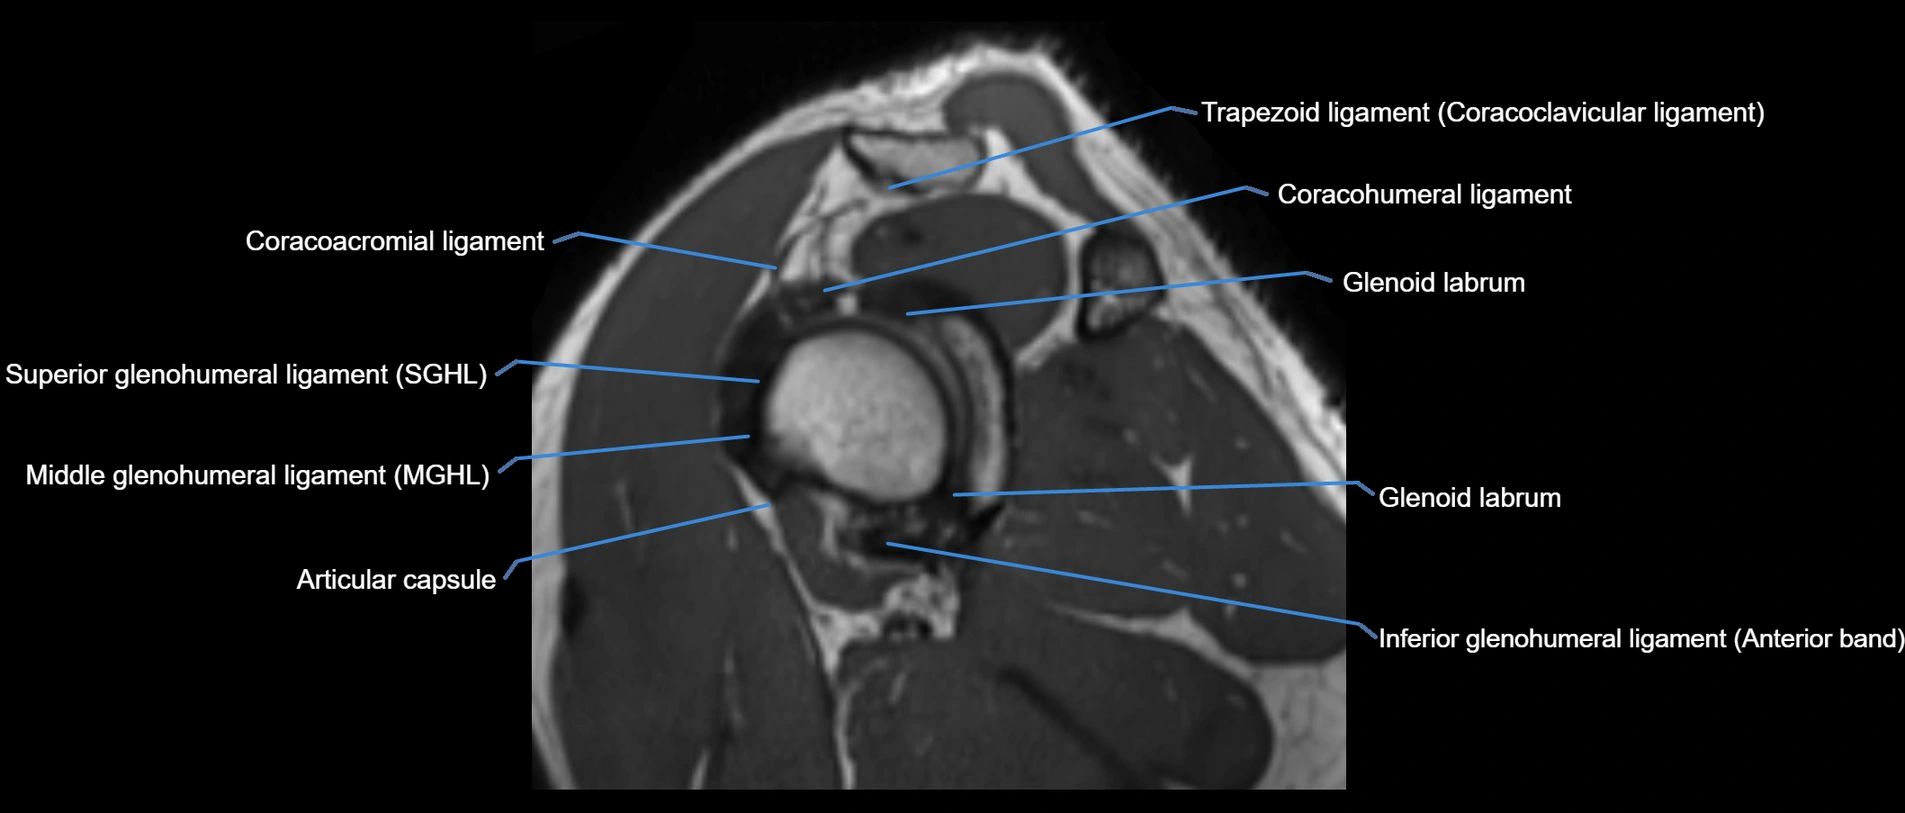

CT image

image